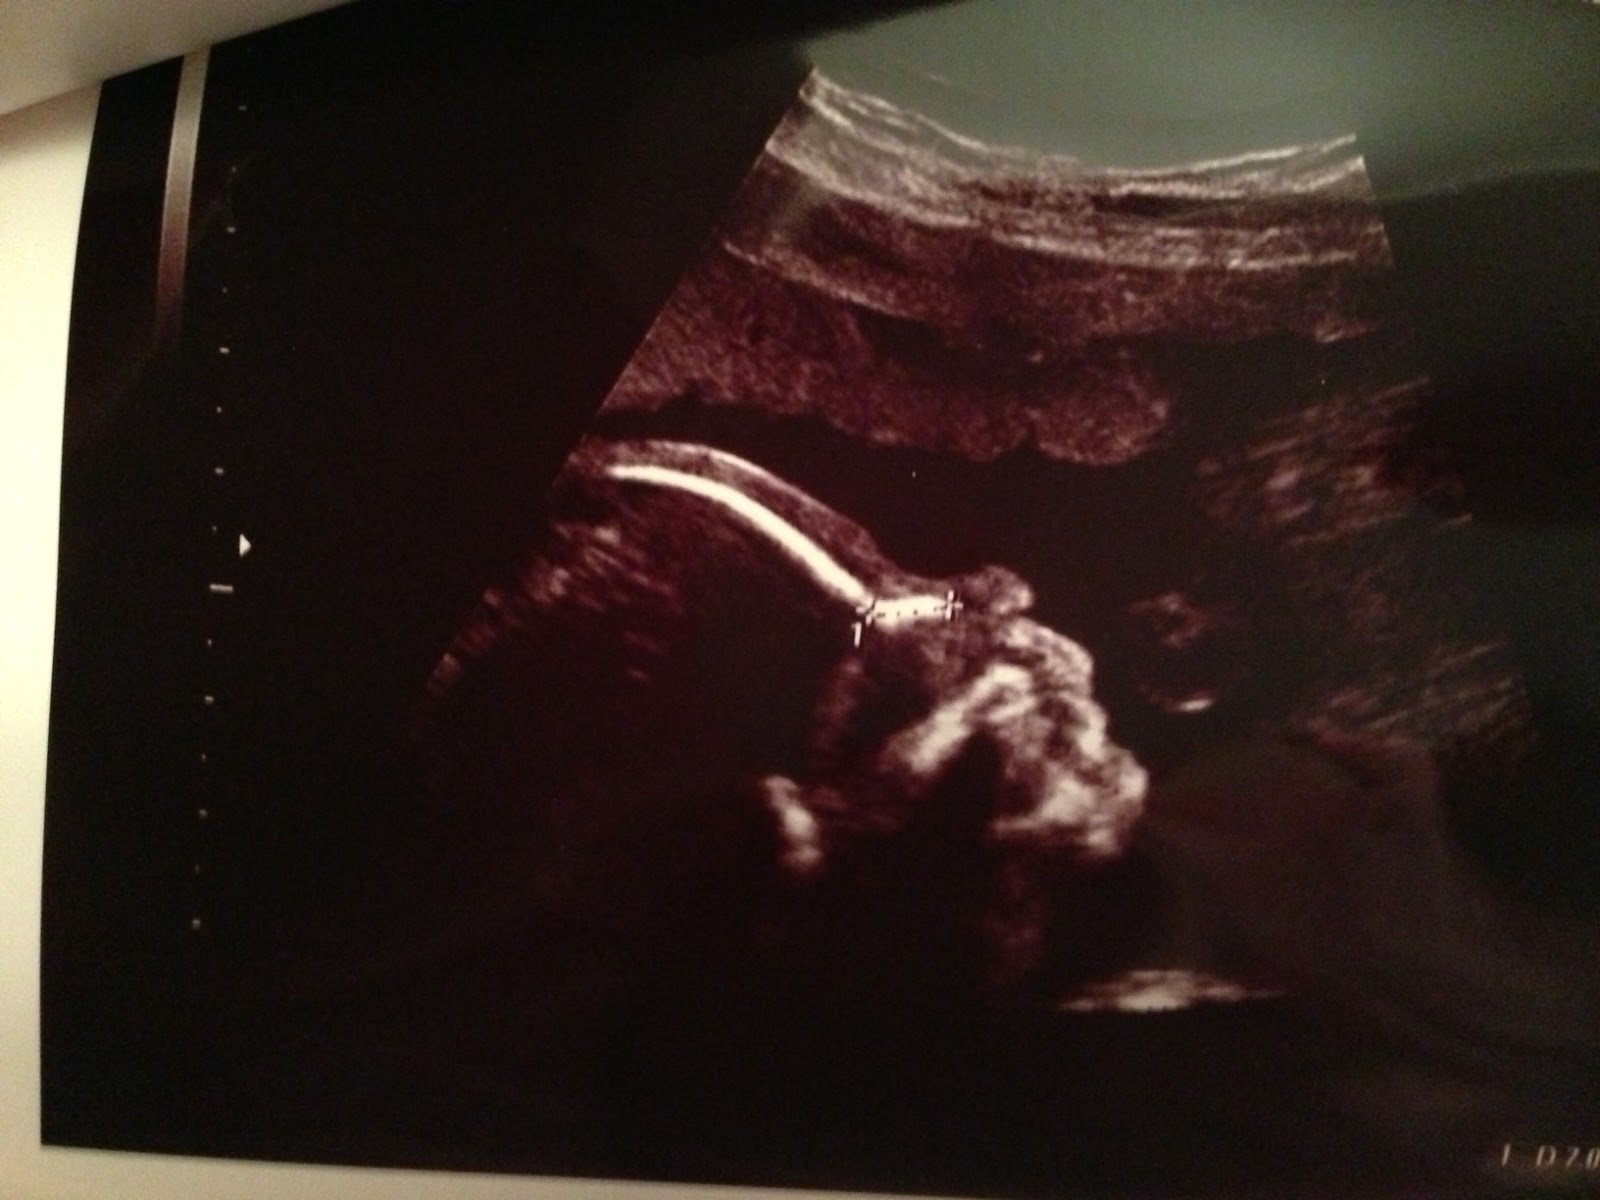

Bu hafta detaylı ultrason günümüz geldi çattı. Biz Nişantaşı’nda Prof. Dr. Atıl Yüksel’e bir ay öncesinden randevumuzu almıştık. Daha doğrusu Kübra Hanım bizim için bu işlemi halletmişti. Okulda tam yedi derse girip çıktığım halde kendimi hiç yorgun hissetmeyişimin sebebi de biricik oğlumuzu görecek olmamdı. Karın böyle bariz şişince muayenehanenin bekleme kısmındaki muhabbetler de çok enteresan oluyormuş. Birbirine yiyecek ikram edenler, tanışanlar (herkesin anlatacak çok şeyi var), uzaktan uzağa süzmeler vs. ☺

Tuncay’ın da katılmasıyla odaya geçtik. Atıl Bey çok tatlı, sevecen bir doktor. Fakat işte her doktor gibi terimlerle konuşurken Tuncay ile bana da bebeğin hareketlerini izleyip birbirimize gülümsemek düştü. Daha sonra bize dönerek ne demek istediğini, az önce söylediği anlamakta zorlandığımız bütün her şeyi teker teker anlattı. Her şey normalmiş. Sadece en baştan beri aydınlatamadığımız ilk adet tarihimiz daha da karmaşık bir hal aldı. Kübra Hanım’ın dediğine göre 14 Nisan’da döllenme gerçekleşmişti. Atıl Bey ise bebek bu tarihten on gün daha büyük gözüktüğünü ama iri bir bebek olmadığını söyledi. Yani tarih biraz ileri olabilir. Bebeğimiz beklediğimizden erken gelebilirmiş. Oleyyyy ☺

Zaten çok özlüyoruz. Böyle bir şey olursa da hayır demeyiz. İşte bizim tatlı oğlumuzun son hali: